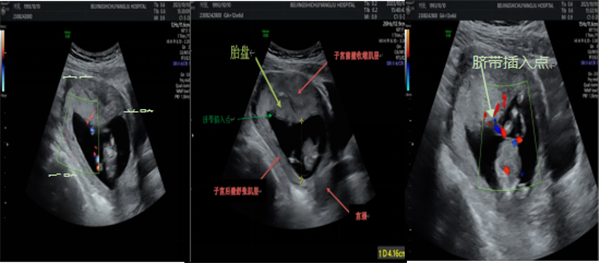

据统计在早孕期约20%-50%胎盘覆盖或毗邻子宫颈内口。如图1超声在早期产前筛查时可以观察胎盘,一般会描述其位置,在前壁、后壁还是宫底,在超声图1中胎盘位于后壁,覆盖宫颈内口。此图可以为整个孕期胎盘定位及临床急症处理时做参考。

▲绿色箭头:覆盖宫颈内口的后壁胎盘;

红色箭头:宫颈内口

胎盘下缘与子宫颈内口的相对位置关系随妊娠及产程的进展而变化称为胎盘迁移。如树根在干涸的地方会枯萎或深扎,向水和营养丰富的区域延伸扩展。如图2-3所示,同一孕妇胎盘位置改变,其胎盘位置从早孕期的前壁宫底到孕晚期后壁为主,胎盘脐带插入点从相对正常位置发展成脐带位于胎盘边缘处的球拍状胎盘。有可能就是在迁移过程脐带插入点一侧胎盘逐渐萎缩。

▲孕12+周 前壁宫底胎盘,脐带插入点略偏向一侧

▲孕28+周、孕32+周 后壁胎盘,脐带插入点位于胎盘上缘边缘处